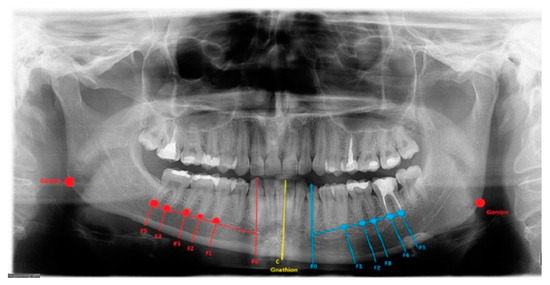

Figure 2.

Severe form of condylar hyperplasia.

The length between Go-Gn/Go-Gn and the vertical bone volume relation decreases the bone height on the opposite healthy side—the critical point of this technique is the distance between the Go-Go/Go-Gn position and the value of the F0-C bone index. In this case, approach 1C can be used with or without corrective angulotomy/anguloplasty, which reduces the angled volume on the affected side in vertical and horizontal dimensions. If both Go (Right) and Go (Left) are situated on the same horizontal line, no major surgery should be planned, unless performing a condylectomy might relocate the Go point on the affected side to a higher position afterward. Therefore, careful planning in the horizontal plane and the F5: Go measurement can help estimate whether any additional mandibular angle surgery should be planned (Figure 1 and Figure 2; Table 1). This was used in some of the authors’ cases where there was no maxillary bite-plane deviation, and no chin bone asymmetry was present.

The authors conclude that a very severe mandibular overgrowth with increased chin involvement should be a mandatory indication for the classic Ferguson approach with a surgical reduction in the mandibular angle on the affected side [7,13]. The main reason for this is the increased distance and height of the F0:F1 and F0:C:F0 values in this study (Figure 1). The authors fully agree with Ferguson’s approach, which is confirmed in the author’s measurements based on the suggested ARP: IM values and the distances between reference points in the presented study radiographs. Two different cases of one-sided mandibular overgrowths in hemimandibular hyperplasia are drawn and explained in Figure 2.